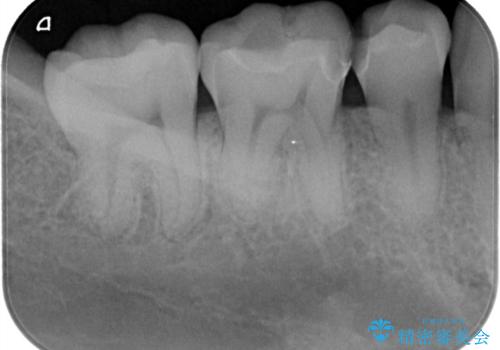

- 「銀歯を白しくしたい」を主訴に来院された患者さんです。

銀歯を外し、虫歯を除去した後にハイブリッドインレーで治療を行いました。

ハイブリッドインレーはセラミックと合成樹脂が混ざったものです。従って経年劣化や色の変化はあるものの、保険適応の被せ物に比べ、セラミックの含有率が高く、型取りの材料もシリコン材料を使用出来るので適合も優れています。